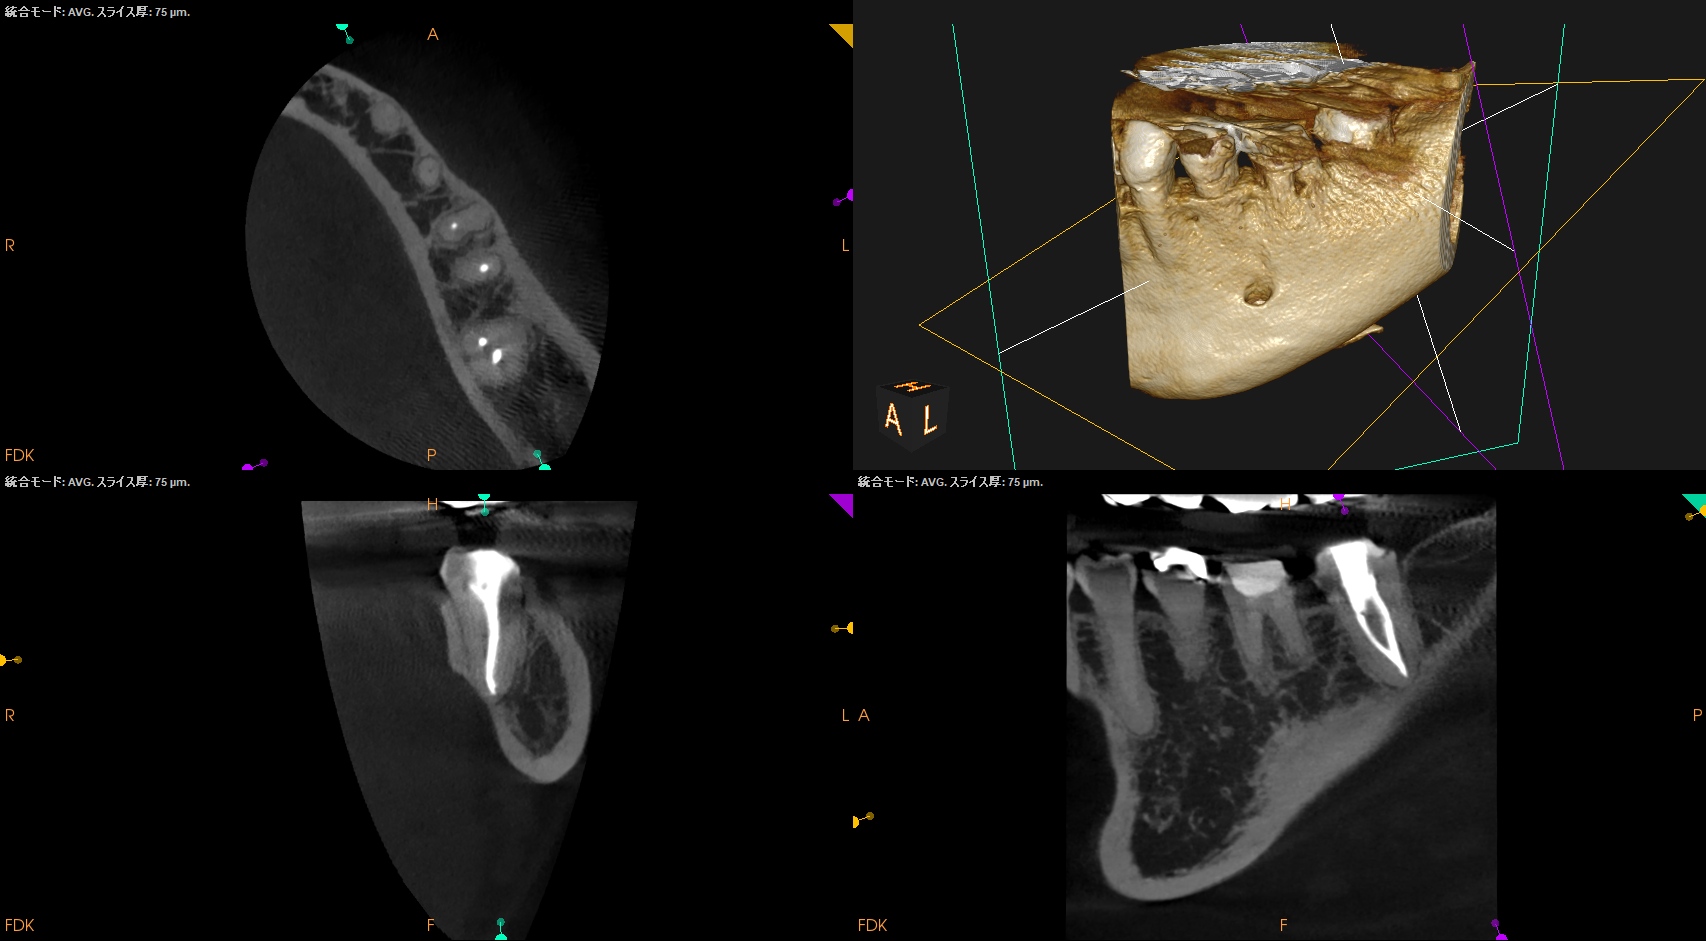

ということで臨在歯の#18もCBCTを精査した。

#18

M

D

#18 Mのこの絵は縁下カリエスの可能性を示唆している。

ではそれになぜ気付けたか?だが、

明らかにCBCTの存在がなければこの存在に気づけなかっただろう。

このことからも、

もはやCBCTの存在は歯内療法においてはマストである

ということがわかる。